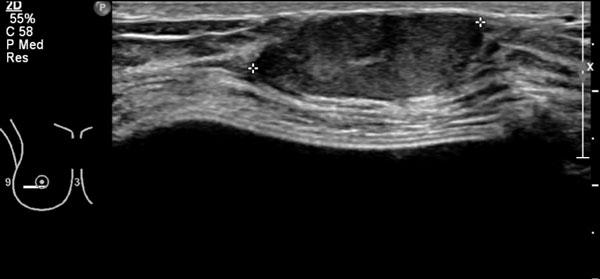

Đây là một trường hợp u xơ tuyến vú điển hình khác.

Lưu ý rằng bờ tổn thương có dạng múi nhẹ.

Người phụ nữ này có túi độn ngực, được thấy dưới dạng các cấu trúc chứa dịch.

Các túi độn được đặt phía sau cơ ngực lớn.

Cuộn hình ảnh để xem chú thích.